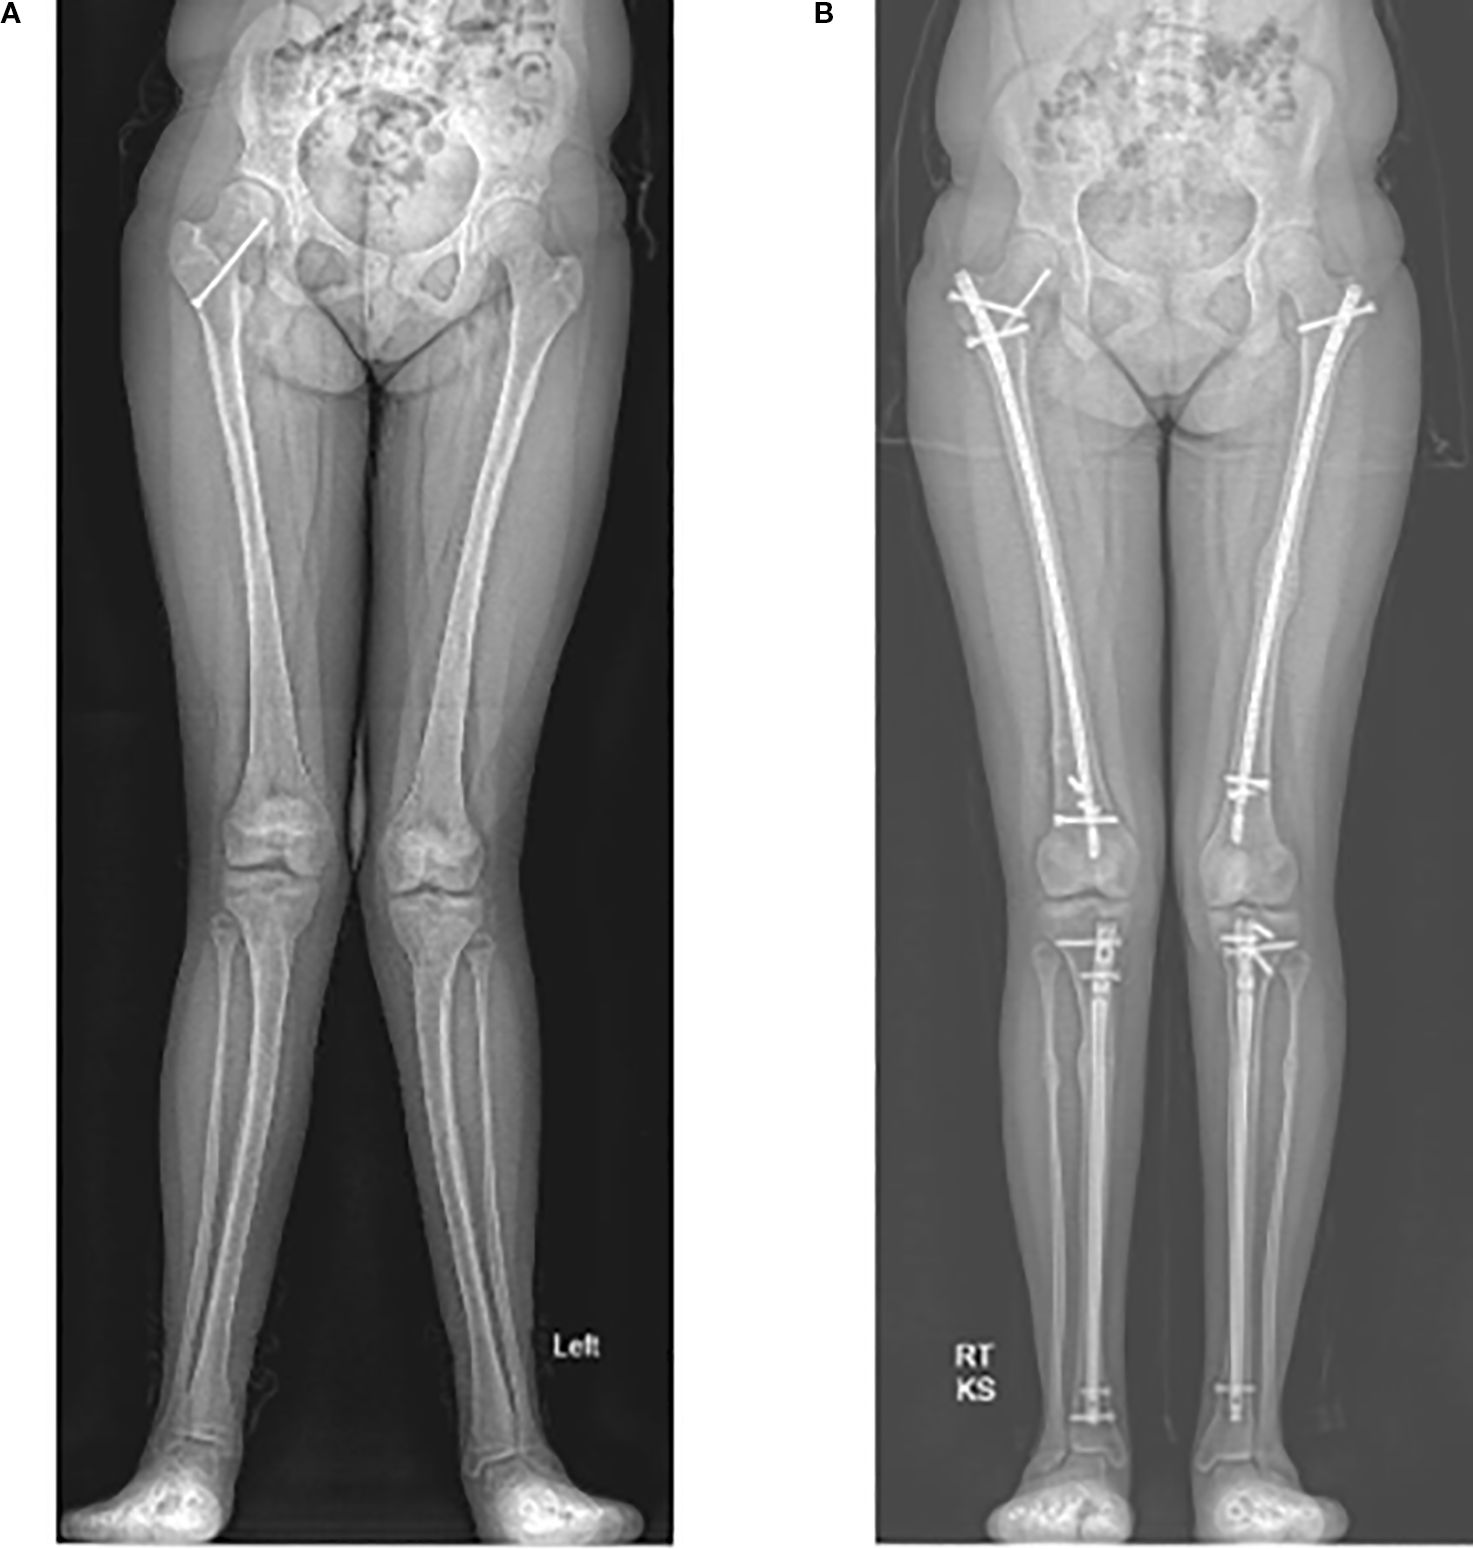

If deformity correction is not achieved with guided-growth procedures, the child may be indicated for formal osteotomy and deformity correction (Figure 3). Additionally, if the patient presents near or at skeletal maturity, guided-growth procedures are ineffective, and the surgical treatment options are limited to formal osteotomies. Fixation can be done with a plate and screws, an intramedullary nail, or, if gradual correction of the deformity is indicated, an external fixator. Internalized hardware can remain for the duration of the patient’s life or be removed if bothersome, while external fixation will be removed once the deformity is corrected, and the bone has healed.

Figure 4. Radiographs of a 12-year-old with significant genu valgum (A). She underwent left sided corrective osteotomies and intramedullary nailing of both the femur and tibia at 13 years old. She then underwent right sided deformity corrections at the age of 14. Radiograph of the corrected lower limb alignment at 15 years old (B).